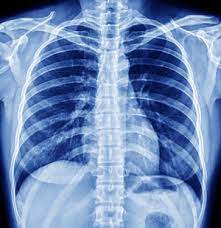

The digital X-ray experience was a revelation. Unlike traditional methods, digital X-rays offer immediate results, significantly reducing wait times and allowing for quicker diagnosis. The high-resolution images provide unparalleled clarity, ensuring that even the minutest details are captured, minimizing the risk of misdiagnosis. For Sanya, this meant peace of mind and a clear path forward in her treatment journey.

Sanya's first visit to the imaging center was a testament to the power of digital X-rays. Greeted by a friendly technician, she was guided through the process with ease. The digital X-ray machine, sleek and modern, required minimal positioning adjustments, making the experience comfortable and hassle-free. Within minutes, the images were ready, and Sanya's doctor could assess her condition with precision.

The clarity and detail of the digital X-ray images allowed the doctor to pinpoint the exact nature of Sanya's ankle issue. With an accurate diagnosis in hand, Sanya was able to embark on a targeted treatment plan. Her journey of recovery was swift, and she soon found herself back on her feet, ready to take on the world with renewed vigor.